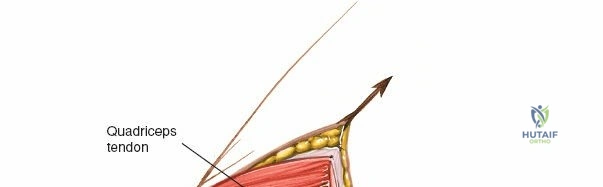

The extensor mechanism comprises the quadriceps femoris muscle group, the quadriceps tendon, the patella, the patellar tendon (ligament), and its insertion into the tibial tubercle.

* Quadriceps Tendon: The confluence of the rectus femoris, vastus lateralis, vastus medialis, and vastus intermedius. The medial parapatellar approach involves an incision extending into the medial aspect of the quadriceps tendon or a separation between the vastus medialis and rectus femoris.

1. Skin Incision

The incision typically begins approximately 3-5 cm proximal to the superior pole of the patella, curves slightly medially along the patellar border, and extends distally parallel to the medial border of the patellar tendon, terminating approximately 2-3 cm distal to the tibial tubercle. A straight midline longitudinal incision is an alternative, particularly when combined with a medial parapatellar capsular approach for TKA, offering a large exposure. The length and curvature of the incision are tailored to the specific procedure and patient anatomy.

Initial skin incision marked, extending proximally along the quadriceps, medially to the patella, and distally along the patellar tendon.

* Quadriceps Tendon: The proximal extension of the arthrotomy enters the quadriceps tendon. A limited "quadriceps snip" can aid in patellar eversion without significantly weakening the tendon.

Proximal extension of the arthrotomy, showing incision into the quadriceps tendon to facilitate further exposure.